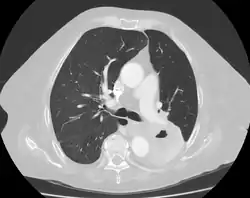

Diagnosis of a lung cavity is made with a chest X-ray or CT scan of the chest,[2] which helps to exclude mimics like lung cysts, emphysema, bullae, and cystic bronchiectasis.[5] Once an imaging diagnosis has been made, a person’s symptoms can be used to further narrow the differential diagnosis. For example, recent onset of fever and productive cough suggest an infection, while a chronic cough, fatigue, and unintentional weight loss suggest cancer or tuberculosis.[2] Symptoms of a lung cavity due to infection can include fever, chills, and cough.[5] Knowing how long someone has had symptoms for or how long a cavity has been present on imaging can also help to narrow down the diagnosis. If symptoms or imaging findings have been present for less than three months, the cause is most likely an acute infection; if they have been present for more than three months, the cause is most likely a chronic infection, cancer, or an autoimmune disease.[5]

In the 2008 Fleischner Society "Glossary of Terms for Thoracic Imaging", a cavity is radiographically defined as “a gas-filled space, seen as a lucency or low-attenuation area, within [a] pulmonary consolidation, a mass, or a nodule”.[9] Pathologically, a cavity is “usually produced by the expulsion or drainage of a necrotic part of the lesion via the bronchial tree.”[9]